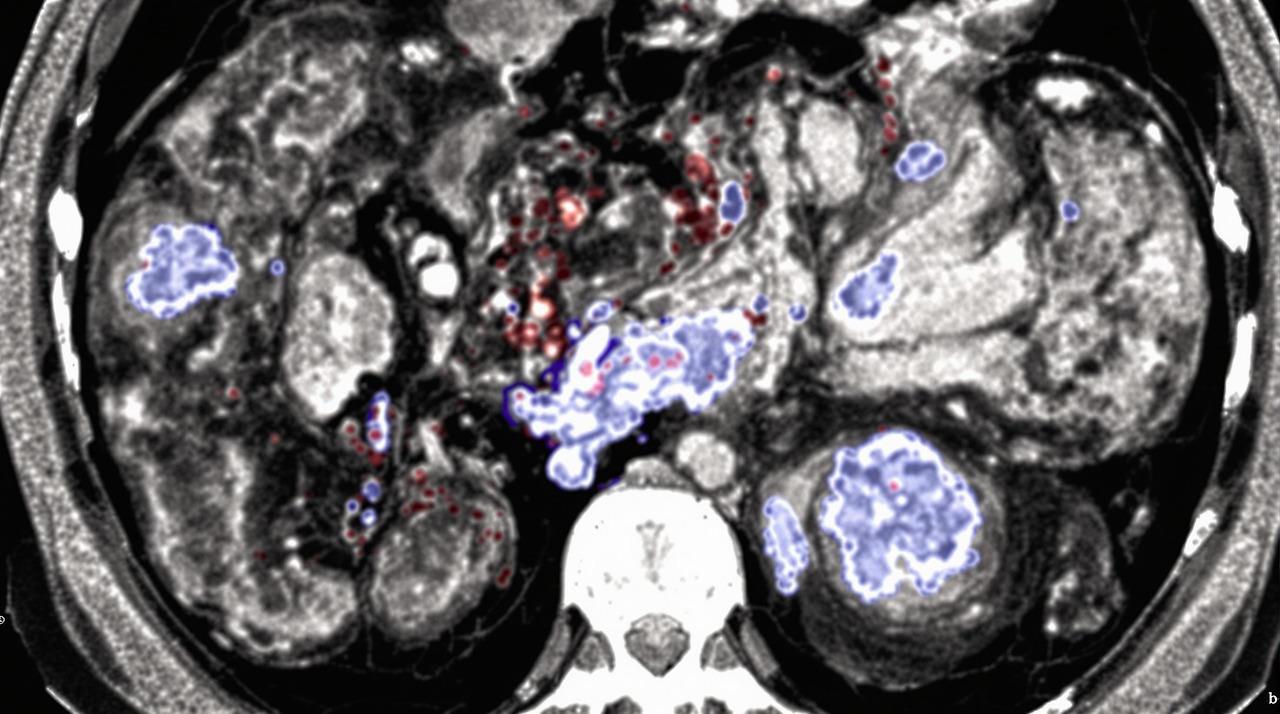

영상 검사는 대장 게실염 진단의 핵심입니다:

- CT 스캔: 게실염 진단의 가장 정확한 방법으로, 게실의 위치와 개수, 염증 정도, 합병증 여부를 확인할 수 있습니다. 조영제를 사용한 CT 검사는 정확도가 약 98%에 달합니다.

- 초음파 검사: 비침습적이며 방사선 노출이 없어 임산부나 젊은 환자에게 유용합니다. 그러나 CT에 비해 정확도가 낮고 검사자의 숙련도에 따라 결과가 달라질 수 있습니다.

- MRI: CT에 비해 비용이 높지만, 방사선 노출 없이 상세한 영상을 제공합니다. 특히 누공이나 복잡한 합병증 평가에 유용합니다.

- 대장 내시경: 급성기에는 천공 위험이 있어 피하는 것이 좋으며, 주로 염증이 완화된 후 게실의 상태를 확인하거나 다른 질환(대장암 등)과의 감별을 위해 시행합니다.

62세 남성 환자의 사례를 보면, 3일간 지속된 좌하복부 통증과 38.5°C의 발열로 응급실에 내원했습니다. 초기 혈액 검사에서 백혈구 수치가 15,000/μL로 증가했고, CT 검사에서 S자 결장에 다수의 게실과 주변 지방 조직의 염증 소견이 확인되어 게실염으로 진단되었습니다.